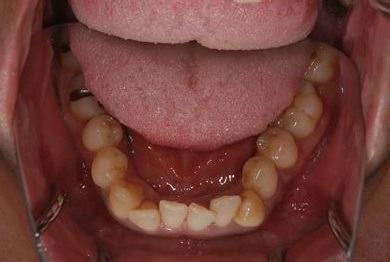

セラミック治療+歯肉歯槽骨整形術

| 性別/年齢 | 男性 / 45歳 | ||||||||||||||||||||||||||||||||

| 主訴 | 詰め物をしている歯が割れてしまったので、治療して欲しい。 | ||||||||||||||||||||||||||||||||

| 治療方針 | セラミック治療にて、審美的回復を行う。 | ||||||||||||||||||||||||||||||||

| 治療内容 | メタルボンドセラミッククラウン1本(メタルボンドセラミック用土台1本)、歯肉歯槽骨整形手術 | ||||||||||||||||||||||||||||||||

| 総治療費 | 157,185円 | ||||||||||||||||||||||||||||||||

| 治療期間 | 7ヶ月 |